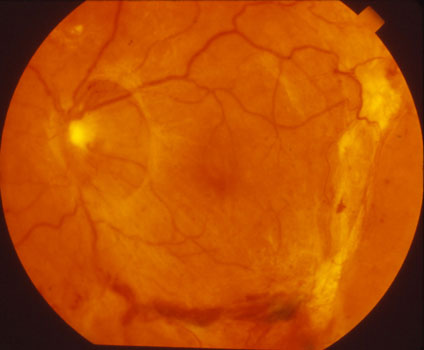

Diabetes can also make the blood vessels close off. Some eyes will develop tiny new blood vessels in an attempt to increase the retinal blood supply (proliferative diabetic retinopathy). These new vessels do not help the eye, however. They are fragile and can cause blindness by bleeding (vitreous hemorrhage) or causing a retinal detachment.

Proliferative diabetic retinopathy